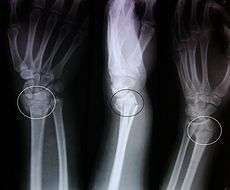

An X-ray image of a fractured radius showing the characteristic Colles' fracture with displacement and angulation of the distal end of the radius

A Colles' fracture is a fracture of the distal radius in the forearm with dorsal (posterior) and radial displacement of the wrist and hand.[1] The fracture is sometimes referred to as a "dinner fork" or "bayonet" deformity due to the shape of the resultant forearm. Colles' fractures are often seen in people with osteoporosis.

The fracture is most commonly caused by people falling onto a hard surface and breaking their fall with outstretched arms - falling with wrists flexed would lead to a Smith's fracture. It can also be caused by overuse. Originally it was described in elderly and/or post-menopausal women. It usually occurs about three to five centimetres proximal to the radio-carpal joint with posterior and lateral displacement of the distal fragment resulting in the characteristic "dinner fork" or "bayonet" like deformity. Colles' fracture is a common fracture in people with osteoporosis, second only to vertebral fractures.